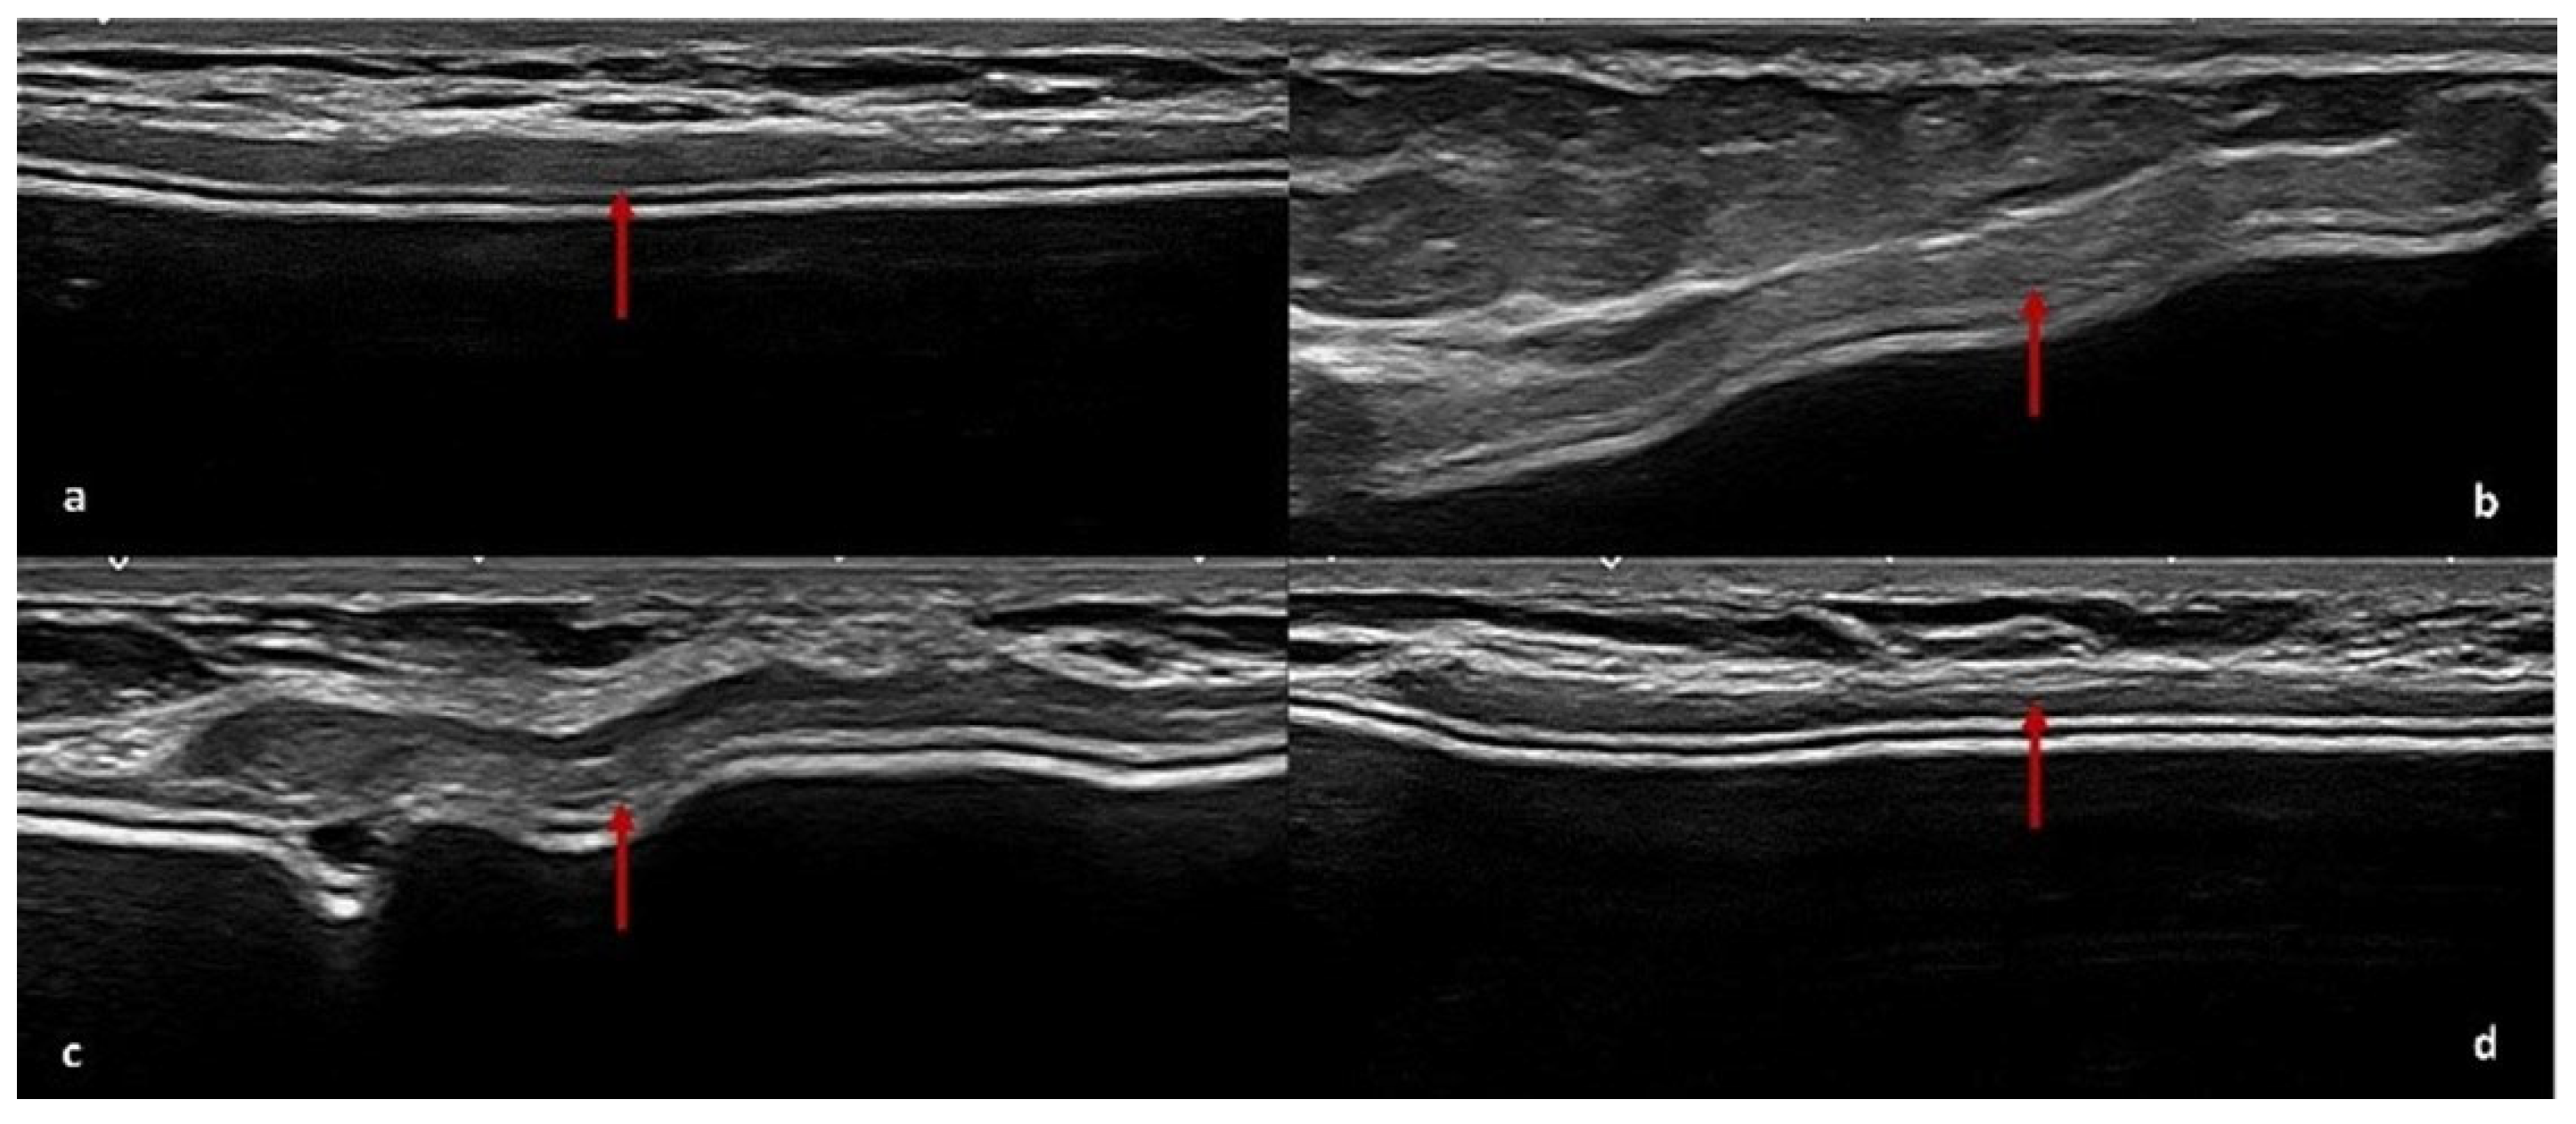

4.2. US Features of ADM

| US | Derived from pig dermis | Ten patients (16%) | Seven patients (11%) | Seven patients (11%) | Five cases of peri-capsular thickening and two cases with pseudonodular areas at T2 |